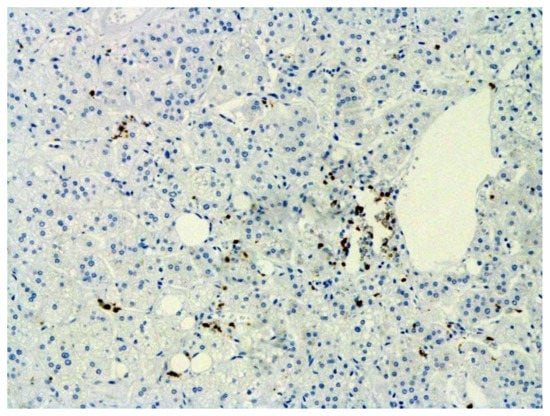

We consider certain changes to be directly related to virus propagation. We succeeded in detecting virus spike antigen in the bronchiolar epithelium (Figure 1) and macrophages (Figure 2) as well.

The hallmarks of apoptosis (according to expression of caspase-3) were revealed in the lungs, lymph nodules, and other organs, predominantly in the area with the small granular rhexis (Figure 4 and Figure 5.) The possibility of developing a generalized infection with damage to other organs is evident. Alterative and necrotic changes were seen in parenchymal cells. Sometimes we noted their changes in the nuclei of the cells in the lymph nodes, intestines, soft meninges, heart, pancreas, kidneys, and spleen. We succeeded in detecting spike and nuclear antigen of the virus in the lymph nodes (Figure 6), pancreas, brain (Figure 7), and adrenals. We described certain lesions in the adrenals that are probably associated with the SARS-CoV-2 virus [25].

Figure 6. Nuclear antigen of SARS-CoV-2 (arrow) in lymph node. IHC ×400.